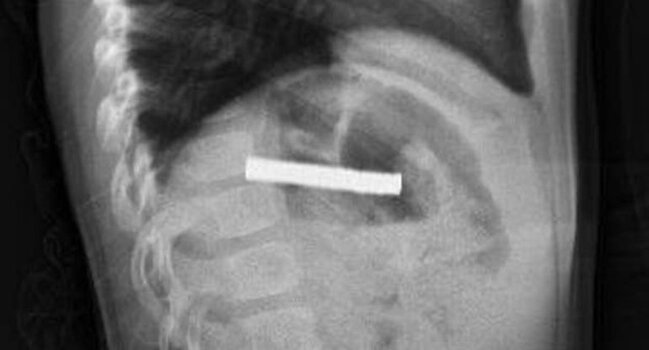

Türkiyədə 3 yaşlı uşağın boğazından 19 ədəd maqnit çıxarılıb.

Ölkə.az xəbər verir ki, Ərzurumda uşaq evdə tapılan 19 maqniti udub.

Fırat Universitetinin Uşaq Qastroenterologiyası, Hepatologiya və Qidalanma kafedrasının müdiri Prof.Dr.Yaşar Doğan endoskopik üsulla uşağın qida borusuna ilişib qalmış 19 maqniti çıxarıb.

Maqnitlər uzun müddət qida borusunda ilişib qalıb, yemək borusu və mədə girişində zədələr yaranıb.